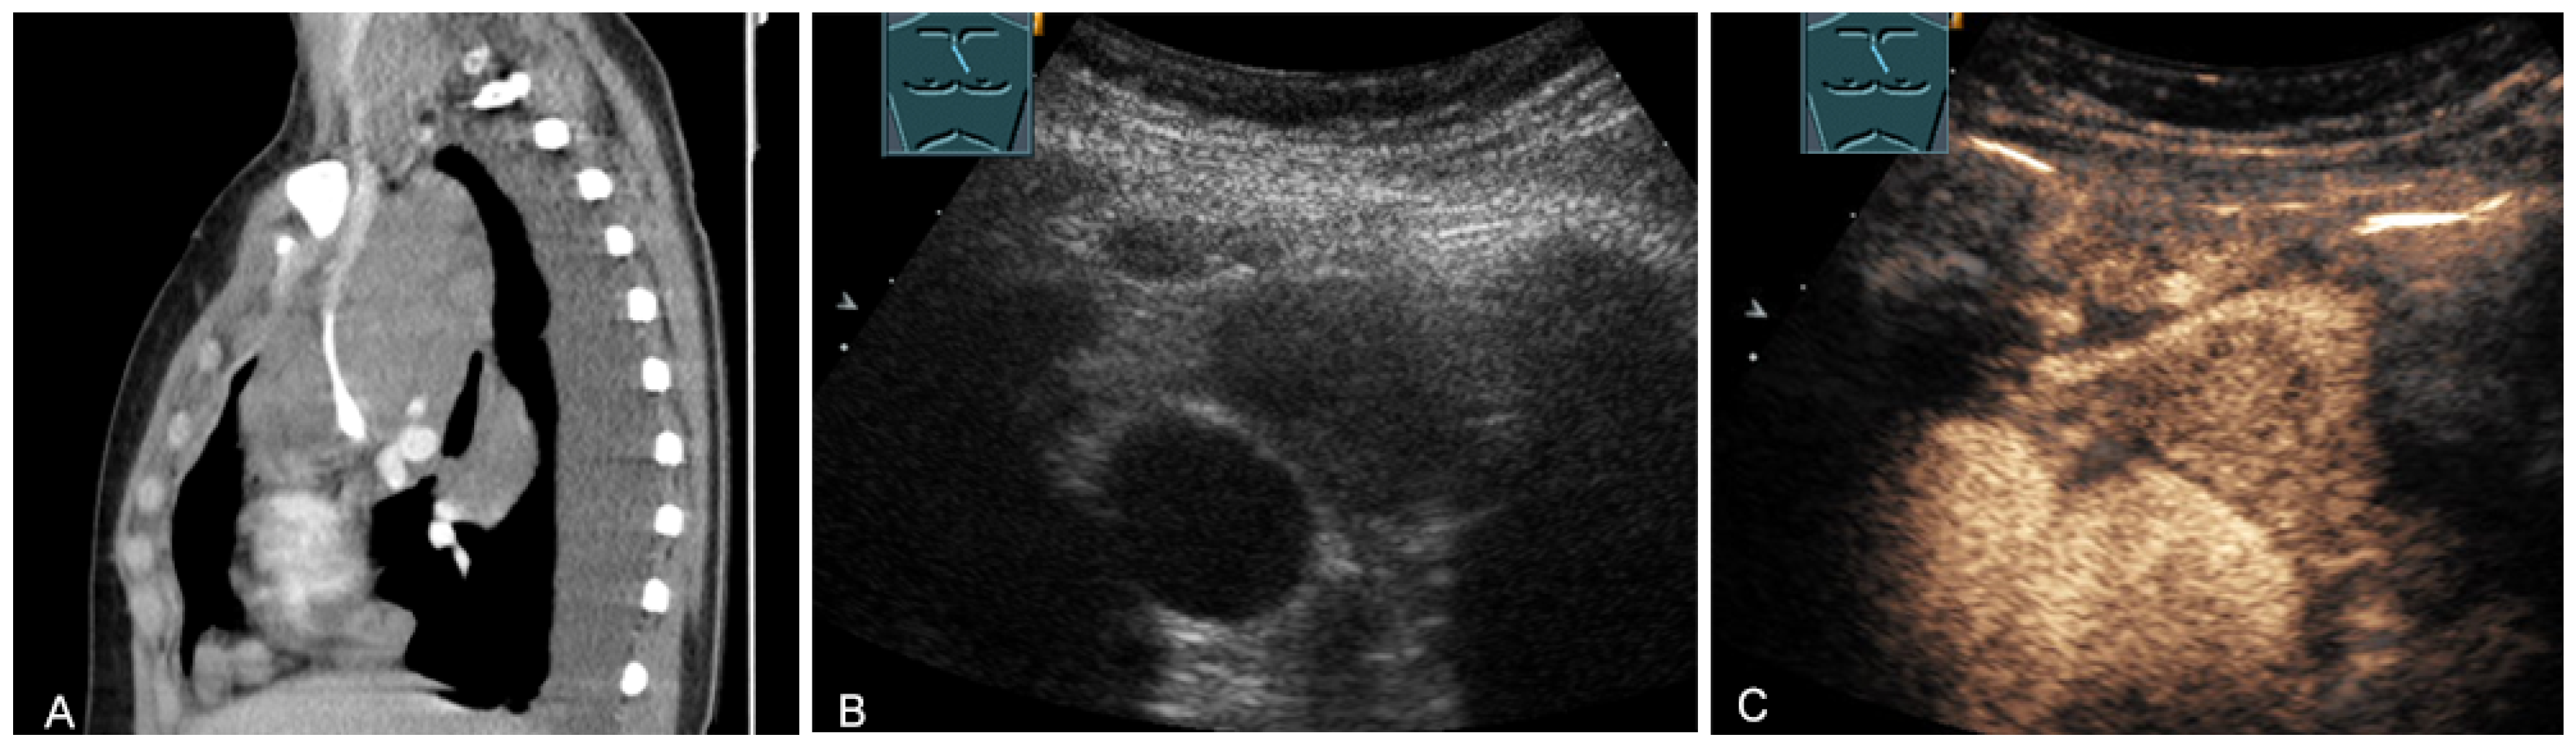

Figure 14.

A cystic mediastinal mass on CT (provided by Prof. Dr. Andreas H. Mahnken, Marburg, Germany) (A), B-mode US (B), and CEUS (C), surgically confirmed as a mediastinally located bronchogenic cyst.